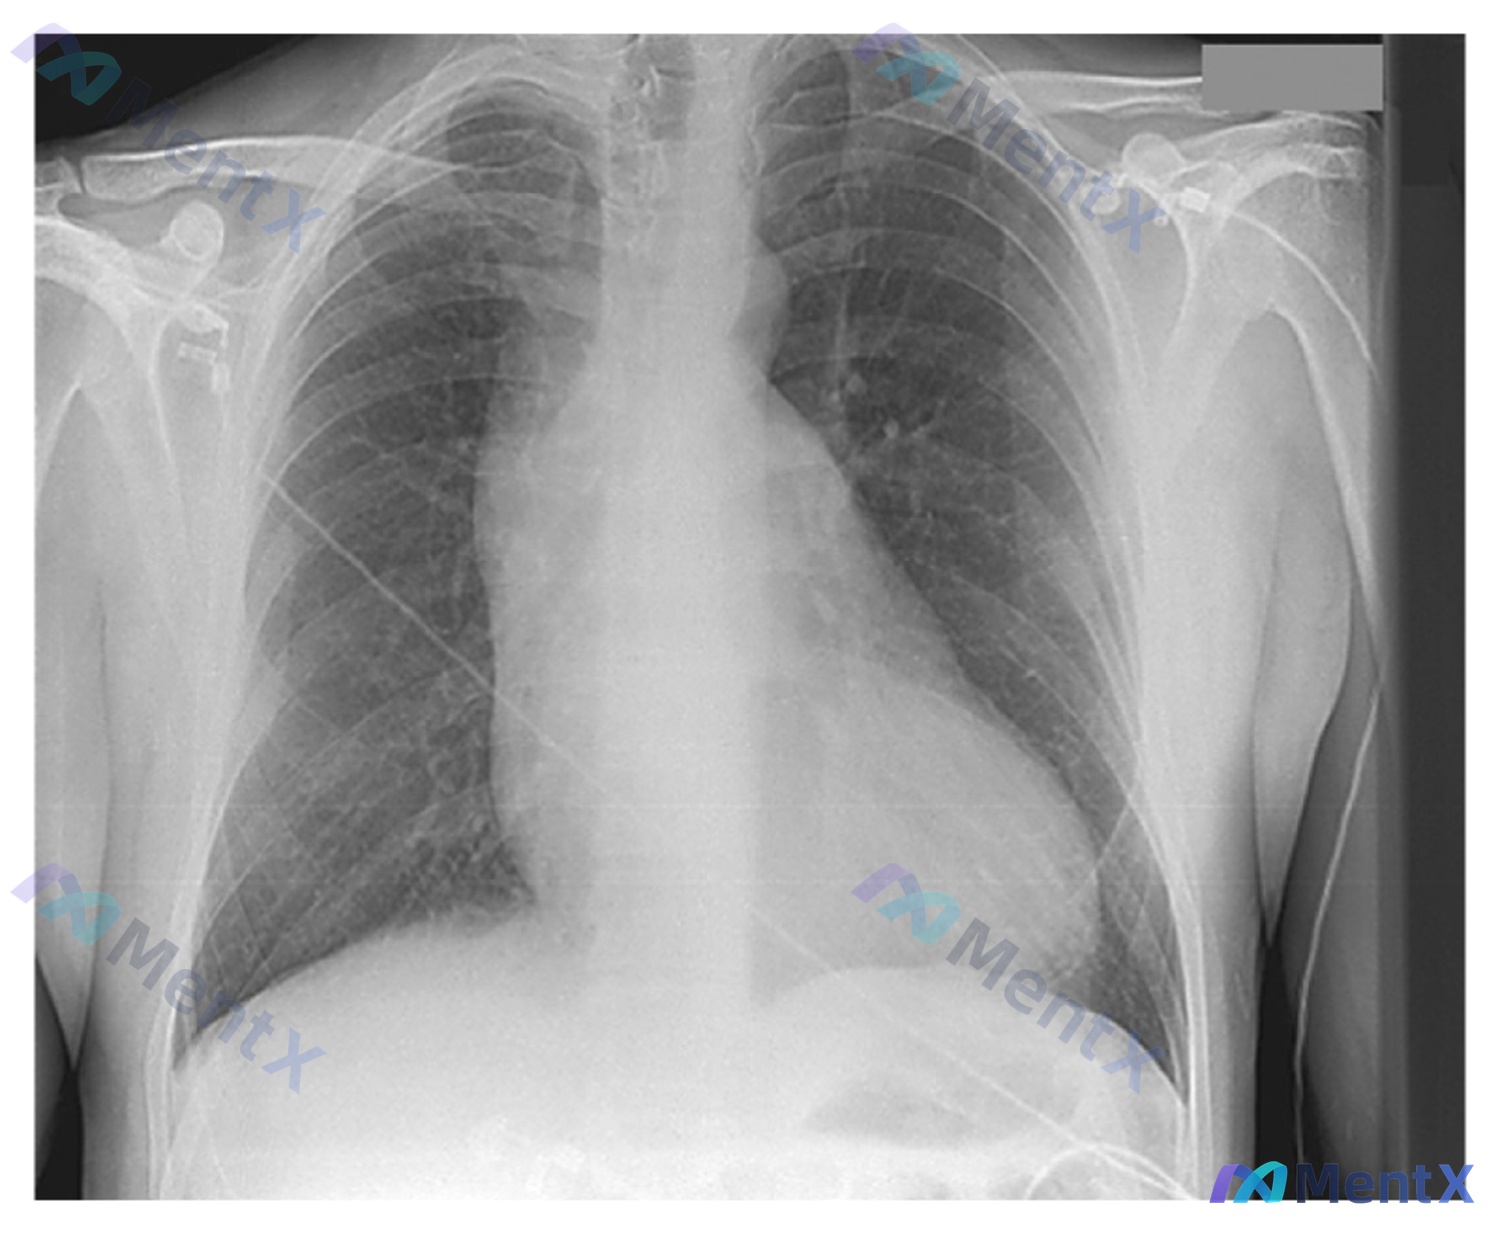

整理了一个挺有警示意义的胸痛病例资料,结合影像和分析说一下思路。 病例核心信息 - 主诉:胸痛 - 关键影像(胸部正位X线): 1. 气道与纵隔:气管居中;主动脉结增宽向左突出,边缘见钙化;纵隔稍增宽;心影明显向两侧扩大,左心缘向左下延伸,心尖圆钝,呈「靴形心」改变。 2. 肺野与胸膜:双肺纹理走行...